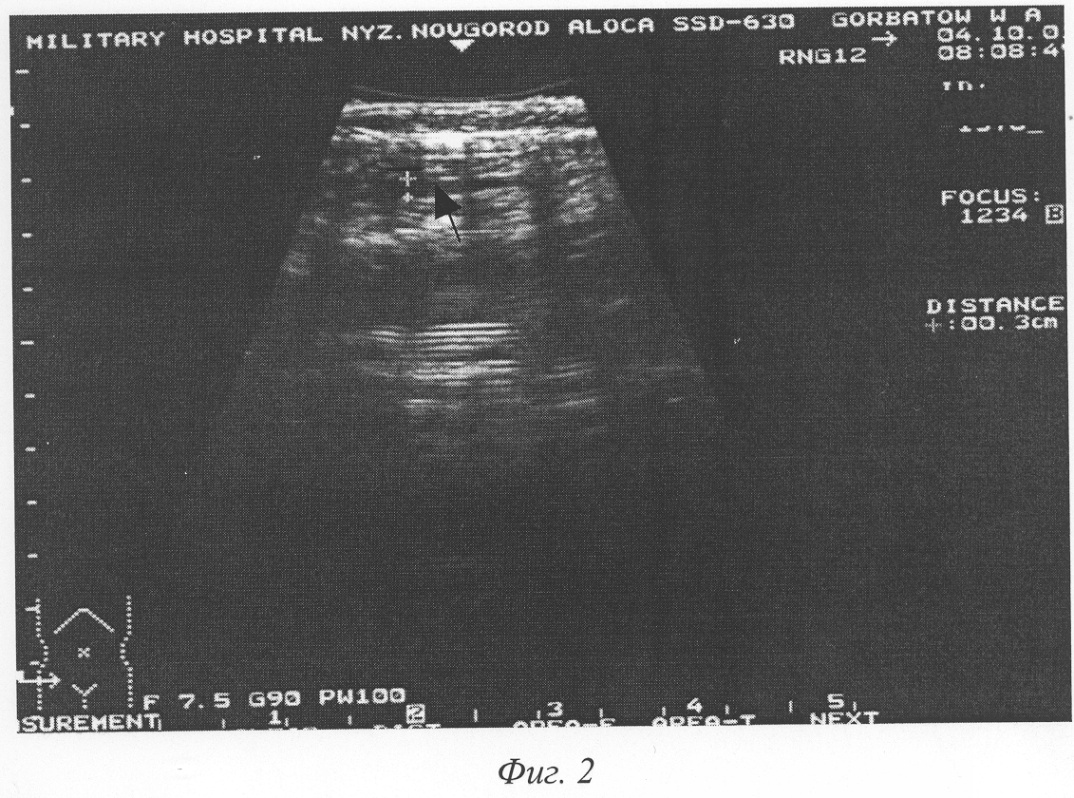

Фиг.2 – эхограмма передней брюшной стенки живота на 5-й день после операции этого же больного. Определяется гипоэхогенная зона (обозначена крестами) на глубине апоневроза наружной косой мышцы живота толщиной 3 мм.

Пример 1. Больной С., 20 лет, история болезни №1941, поступил в клинику 22.03.2001 года с диагнозом «Острый аппендицит». Диагноз подтвержден данными анамнеза, объективного обследования и лабораторными показателями. Операция – аппендэктомия. Послеоперационный диагноз: катаральный аппендицит. Операционная рана ушита наглухо. В послеоперационном периоде боли в области раны купировались 24.03.01. Гиперемия в области швов исчезла на 4-е сутки. Средняя температура тела в первые 4 суток послеоперационного периода 37,3°С. При сканировании области послеоперационной раны, на глубине апоневроза на 3-й сутки (25.03.01) гипоэхогенная зона толщиной 5 мм (фиг.1). 27.03.01 г. гипоэхогенная зона в той же области уменьшилась до 3 мм, на 7-е сутки – толщина гипоэхогенной зоны – 3 мм (фиг.2). Швы на коже сняты на 7-й день после операции. Заживление раны первичным натяжением. Выписан в удовлетворительном состоянии.